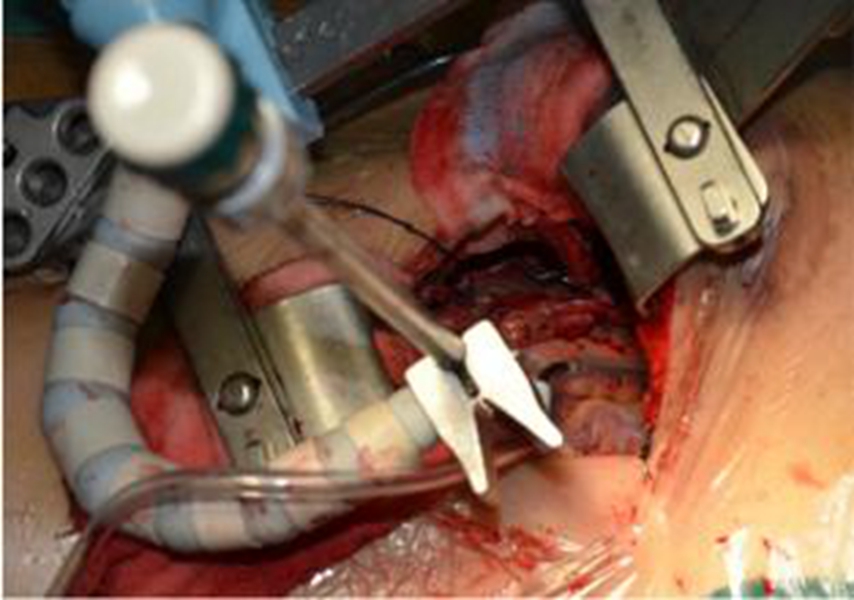

幼兒煙霧病腦手術

幼兒頭部手術煙霧病